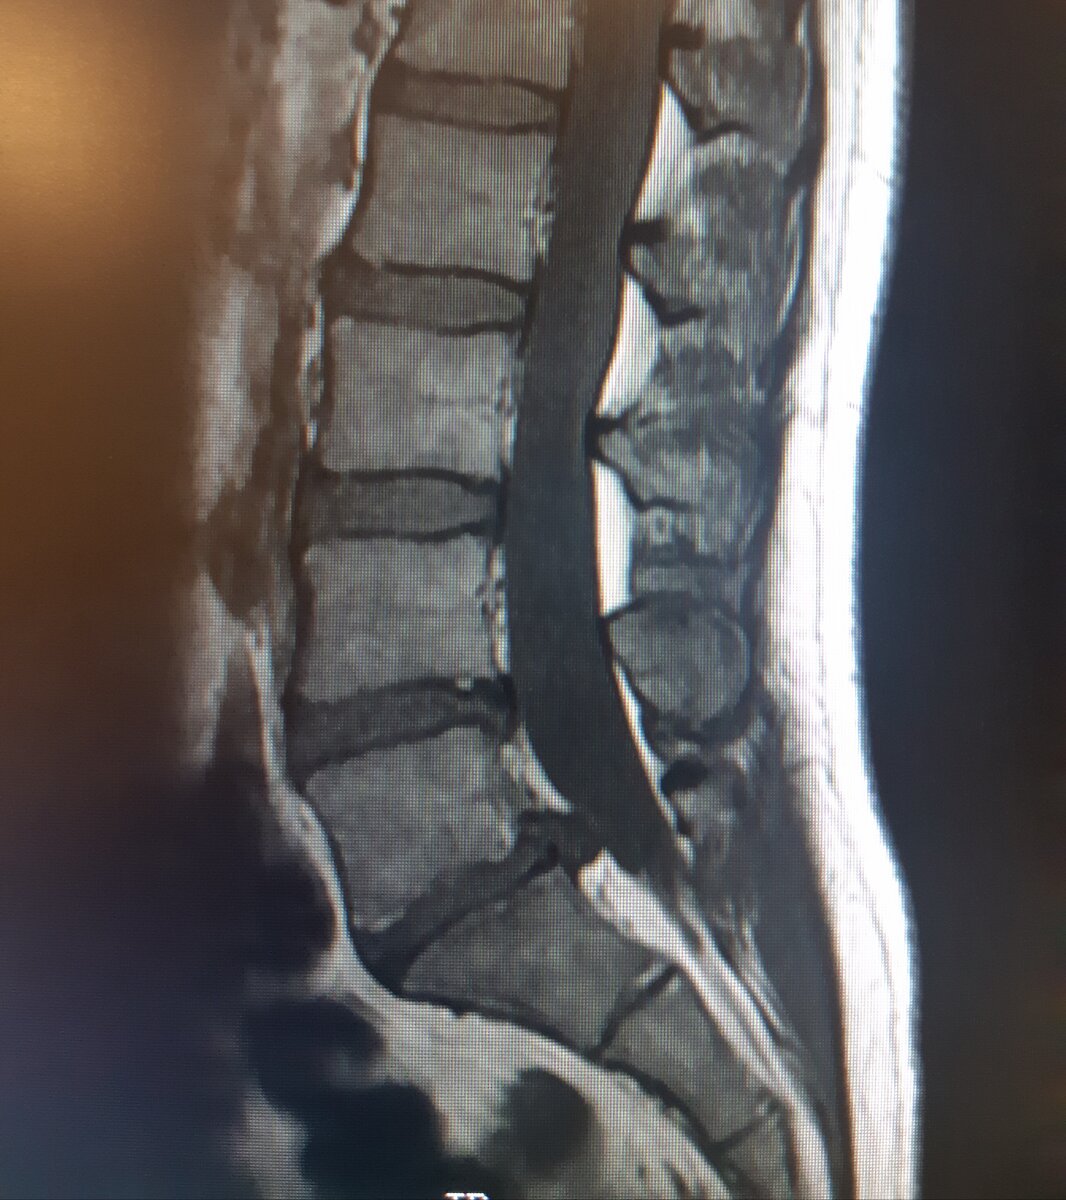

Итак, сейчас у меня две грыжи l5-s1 10 мм и и l4-l5 6мм. Почти три года назад было так: l4-l5 12 мм с секвестром и l5-s1 8 мм. Также имеется смещение позвонка l5 вперед на 4 мм.

Мои родные)